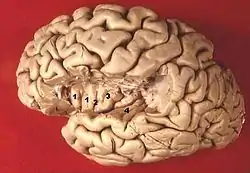

Human brain view on transverse temporal and insular gyri (gyri temporales transversi are #4) | |